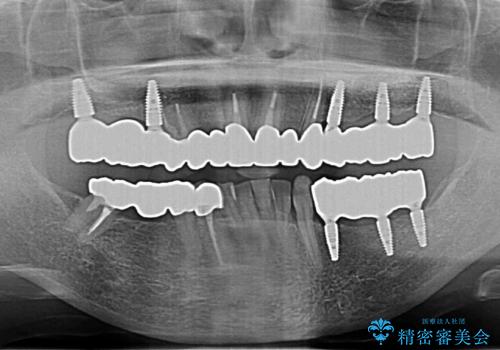

多発した虫歯による咬合崩壊 インプラントを用いた全顎治療

歯の破折・再発した大きな虫歯・根尖病変・歯の欠損、これらの問題を根管治療・歯周外科・インプラント治療・セラミック補綴を行うことで一つづつ解決し安定した咬合状となるよう治療を進めます。

口腔内全体を治療する全顎治療は、期間も長く外科を行う回数も多いためしっかりと通っていただくことが必要不可欠になります。